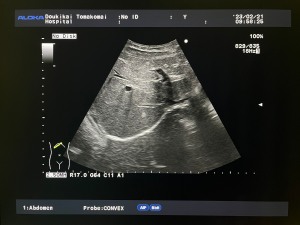

超音波検査(エコー検査)

腹部、乳腺、甲状腺、心臓、血管など調べたい臓器に体の表面から超音波をあてて検査します

エコー検査の写真1

エコー検査の写真2